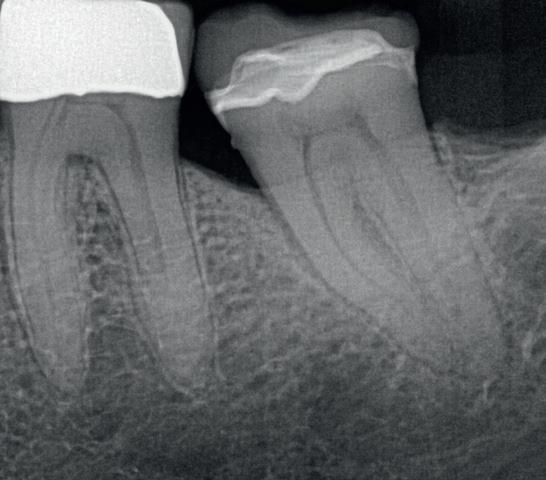

Abb. 4a: Zahn 37: Die präoperative Röntgenaufnahme zeigt eine keramisch adhäsive Versorgung nach Caries profunda, zwei Jahre später: irreversible Pulpitis mit apikaler Parodontitis. –Abb. 4b: Röntgenaufnahme nach der Füllung von Zahn 37: Die endodontische Aufbereitung mit HyFlex EDM OGSF sorgt für schonende Reinigung bei komplexer Kanalanatomie.

Das OGSF-Konzept – also Opener, Glider, Shaper, Finisher – ist logisch aufgebaut, die Feilen sind perfekt aufeinander abgestimmt und „gleiten“ leicht durch den Kanal (Abb. 3). Klinische Bilder und Follow-up-Ergebnisse sehen Sie in einem meiner letzten Patientenfälle, bei dem genau dieses System eingesetzt wurde (Abb. 4a+b).